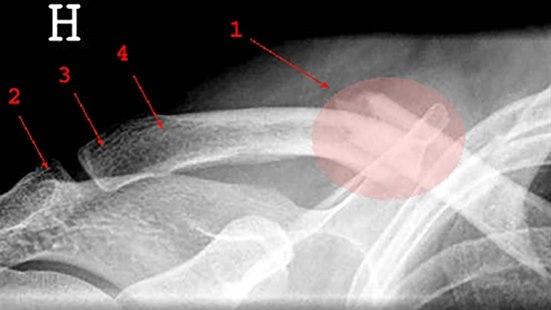

Typiske symptomer på kreagebeinskade er smerte og ømhet. Illustrasjonsbilde: Colourbox

Kragebeinskade

- Et brukket kragebein (clavicula) skyldes vanligvis en indirekte kraft, for eksempel et fall på utstrakt arm

- Dette overfører kraften langs den skadedes underarm og overarm til kragebeinet

- Årsaken kan også være et direkte slag